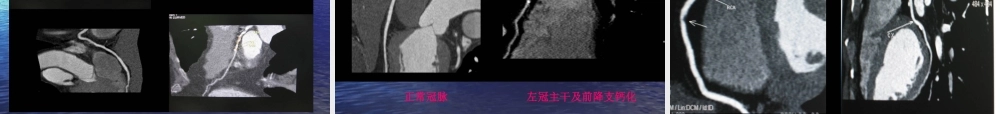

1.MSCT 后处理技术在冠脉疾病检查中的应用2.MSCTMSCT 后处理技术在颅脑、五官疾病检查中的应用3后处理技术在胸部疾病检查中的应用4.MSCT 后处理技术在腹部疾病检查中的应用5.MSCT 后处理技术在血管疾病检查中的应用6.MSCT 后处理技术在骨、关节疾病检查中的应用MSCT 后处理技术1. 实时多平面重建( MPR)2. 曲面重建( CPR)3. 最大密度投影( MIP)4. 最小密度投影( MIN—IP)5.X— 线模拟投影6. 透明化 X— 线模拟投影( 4D )7 表面重建8. 高级三维容积漫游( VRT )9.MSCT 仿真内窥镜( VE)10. 其它多平面重建( MPR)•定义:是从原始横断面图像获得人体相应组织器官任意层面的冠状 . 矢状 . 横轴面和斜面的二维图像的后处理方法。•应用:适用全身各个系统组织器官的形态学改变,尤其对判断颅底 . 颈部 . 肺门 . 纵隔 . 腹部 . 血管等解剖结构复杂部位的病变性质 . 侵及范围 . 彼邻关系和小的骨折碎片和动脉夹层破口及胆道 . 输尿管结石的定位诊断具有明显优势。曲面重建( CPR )•它是 MPR 的一种特殊方式,适用于展示人体曲面结构的器官(如颌面骨 . 骶骨 . 走行迂曲的血管 . 支气管 . 胰腺等)的全貌。最大密度投影( MIP )•它是利用容积数据中在视线方向上密度最大的全部像元值成像的投影技术之一。•其主要优势是可以较真实地反映组织的密度差异,清晰确切地显示经对比剂强化的血管形态 . 走行 . 异常改变和血管壁的钙化以及分布范围,对骨折 . 骨肿瘤 . 骨质疏松等造成的骨质密度改变也较敏感。最小密度投影( Min - IP )•利用容积数据中在视线方向上密度最小的元素成像的投影技术。X— 线模拟投影•是利用容积数据中在视线方向上的全部像元值的投影技术。•重建后的图像效果效果类似于 X 线片。•优势:多角度 . 多方位投影。可去处与靶器官重叠的组织器官影像干扰。•主要用于骨骼病变的显示。透明化 x— 线模拟投影( 4D )•是由 x— 线模拟投影技术衍生出来的以透明方式的图像。•应用:中空器官和骨骼等表面组织结构密度明显高于内部组织密度的器官。如气道 . 食道 . 胃肠道 . 血管 . 长骨 . 扁骨等。高级三维容积漫游( VRT )8.MSCT 仿真内窥镜( VE )•它是一种特殊的三维图像后处理技术,由于该技术重建后的图像效果类似于纤维内窥镜所见,所以称为 CT 仿真内窥镜。•优势: 1 )图像清晰 2 )三维空间关系...